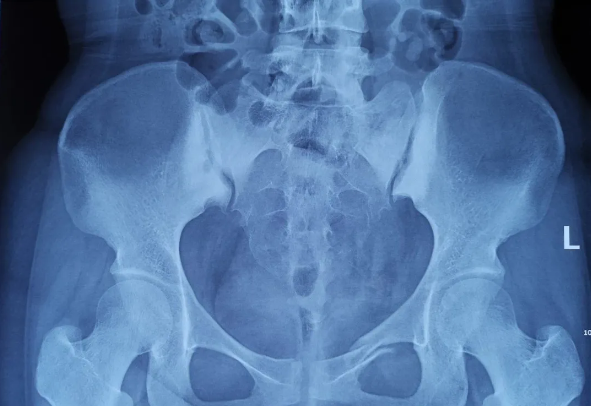

2025-02-28 2025-02-28智匯天璣|高齡不是禁區!北京積水潭醫院智能骨科機器人助力90歲骨盆骨折患者重獲行走由北京積水潭醫院院長蔣協遠、智能骨科研究型病房主任王軍強帶領的智能骨科團隊,運用骨科機器人輔助經皮骨盆通道螺釘置入技術,成功救治了一名90歲高齡的骨盆骨折患者。

2021-01-06 2021-01-06天璣骨科手術機器人落戶南昌市第一醫院,助力骨盆骨折閉合復位內固定術順利完成近日,天璣?骨科手術機器人落戶南昌市第一醫院,助力骨盆骨折閉合復位內固定術順利完成。作為江西省首先采用5G引導下的骨科機器人手術,天璣?骨科手術機器人用它的“透視眼”,以三維影像掃描進行深層三維空間精準定位,為患者“量身定做”了最理想、最安全的教科書般通道,完成了復雜骨盆骨折微創治療一次性完美置釘及腰椎骨折微創經皮置釘的首秀,成為江西省骨科發展的標志性事件,同時也是江西省骨科步入新型數字智慧骨科時代的重要里程碑事件。